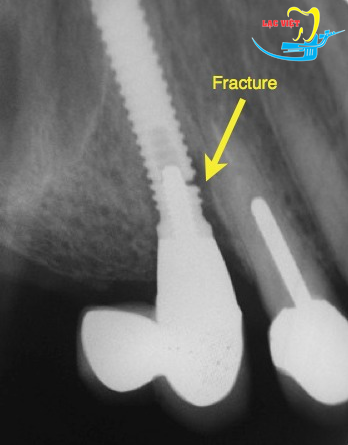

Răng implant bị lung lay do gẫy implant

Răng implant bị lung lay do gãy implant

Một trường hợp gẫy implant

Trường hợp này có thể xẩy ra nếu đặt implant quá bé, đặt biệt là mini implant, kết hợp là tình trạng tiêu xương vùng cổ implant nhiều, lực nhai tác động lên implant lớn làm gẫy implant

Xử trí răng implant bị lung lay do gẫy implant

Nhổ bỏ implant và thay thế bằng implant chính hãng là phương pháp tốt nhất trong trường hợp xấu này xảy ra đối với Quý bệnh nhân